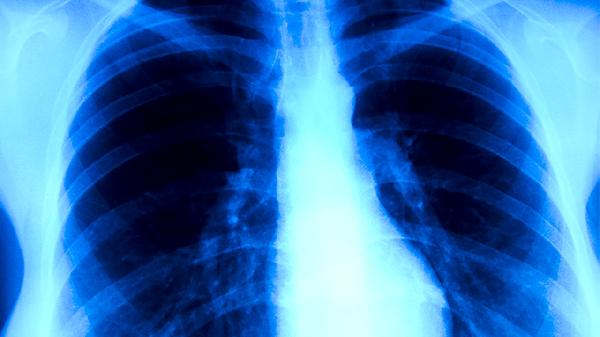

肺癌的常见表现症状主要有咳嗽、痰中带血、胸痛、呼吸困难、体重下降等。肺癌是起源于支气管黏膜或腺体的恶性肿瘤,早期症状可能不明显,随着病情进展症状逐渐加重。

咳嗽是肺癌最常见的早期症状,多表现为刺激性干咳或阵发性呛咳。肿瘤刺激支气管黏膜可引起持续性咳嗽,咳嗽特点为无痰或少痰,常规止咳药物治疗效果不佳。当肿瘤增大阻塞支气管时,可导致阻塞性肺炎,此时咳嗽可能伴有脓性痰液。长期吸烟者如出现持续加重的咳嗽,应警惕肺癌可能。

痰中带血或咯血是肺癌的典型症状之一,表现为痰中带有血丝或小血块。这是由于肿瘤组织血供丰富且质地脆弱,在咳嗽时容易破裂出血。咯血量可从少量血丝到大量咯血不等,中央型肺癌更易出现此症状。当出现不明原因的痰中带血时,应及时就医检查排除肺癌。

胸痛多表现为胸部隐痛或钝痛,在咳嗽或深呼吸时加重。肿瘤侵犯胸膜或胸壁时可引起持续性胸痛,疼痛部位常与肿瘤位置相关。当肿瘤侵犯肋间神经时,可出现沿肋间神经分布的放射性疼痛。晚期肺癌患者可能出现剧烈且持续的胸痛,常需强效镇痛药物控制。

呼吸困难多发生在肺癌中晚期,表现为活动后气促或静息时呼吸困难。肿瘤阻塞大气道可导致通气功能障碍,大量胸腔积液可压迫肺组织影响呼吸。当肿瘤广泛转移至双肺时,可出现进行性加重的呼吸困难。部分患者可伴有喘鸣音,平卧位时症状可能加重。

不明原因的体重下降是肺癌常见全身症状,患者可能在数月内体重减轻超过5%。肿瘤消耗大量能量,同时分泌的细胞因子可导致机体代谢紊乱。食欲减退、吞咽困难等症状可进一步加重营养不良。晚期患者可能出现明显消瘦甚至恶病质状态。

肺癌症状多样且缺乏特异性,长期吸烟者、有肺癌家族史者、长期接触致癌物质者等高危人群应定期体检。出现上述症状时应尽早就医,通过胸部CT、支气管镜等检查明确诊断。确诊后应根据病理类型和分期制定个体化治疗方案,包括手术、放疗、化疗、靶向治疗等。日常生活中应戒烟并避免二手烟,注意保持室内空气流通,适当锻炼增强体质,保持均衡饮食以维持良好营养状态。